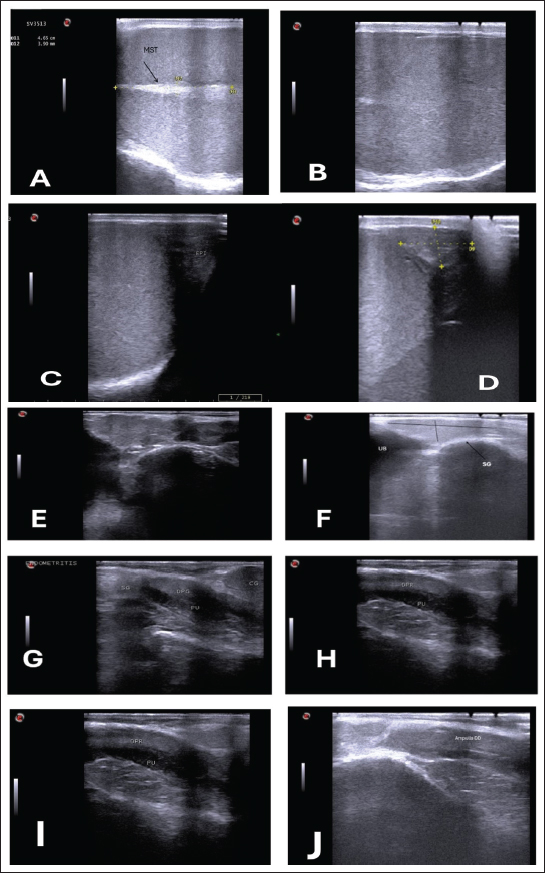

The testicular parenchyma of both ram groups was uniformly echogenic (B-mode) (Fig. 1A), but during the breeding season, the mediastinum testis was large and also more clear compared to out of breeding (Fig. 1B).

Fig. 1. (A) Parenchyma showing uniform echogenicity with large mediastinum tests (length and thickness) and homogenous appearance during the non-breeding season (B), (C) Show large size of epididymis compared to small size during nonbreeding season in(D). (E–H) Show different ecogenicity and variation in the size of male sex gland during breeding and non breeding season. (E) show enlargement and lobulation of seminal gland comparing to loss of lobulation and decrease in its size in (F). (I) also show more clear dorsal part of prostate gland during breeding season.

The tail of the epididymis caught on from a slanting plane near the distal pole of the testis. Ultrasonographic scan of the testis showing the tail of the epididymis. The tail appears to be larger, heterogeneous in echotexture, and less echogenic than the testis, which may be related to distension with semen content during the mating season (Fig. 1C). During the non-breeding season, the tail of the epididymis is significantly smaller and more homogenous, indicating decreased sperm storage activity (Fig. 1D; Table 3).

The sex glands of the rats were evaluated ultrasonographically, and the results declared seasonal fluctuations. Higher secretory activity was reflected in the seminal gland by enhanced echogenicity, more lobulated appearance, and clearly defined margins (heterogenous appearance) throughout the breeding season (Fig. 1E; Table 4). Additionally, compared with the nonbreeding phase, the prostate and bulbourethral glands had a denser echotexture and were marginally more noticeable (Fig. 1G–J). The glands seemed smaller, less distinct, and had a more uniform and diminished echogenic pattern during the non-breeding season as a result of lower functional activity (Fig. 1F).